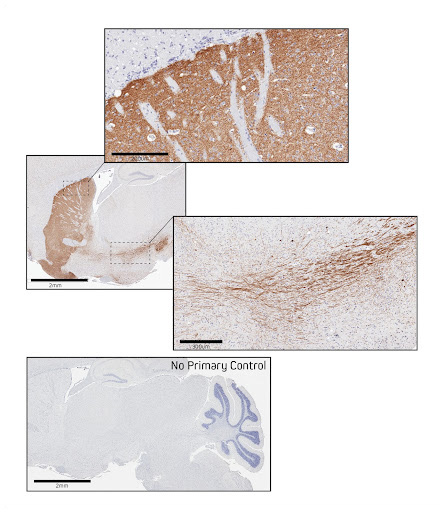

Figure 5. Immunohistochemistry in formalin-fixed paraffin-embedded (FFPE) mouse brain for Tyrosine Hydroxylase. Sagittal sections of mouse brain were blocked with 5% normal Alpaca serum in Tris buffer. Primary antibody, Rabbit anti-Tyrosine Hydroxylase used at a 1:250 dilution at 4C overnight. Secondary antibody, AffiniPure-VHH™ Secondary Biotin-SP VHH Fragment Anti-Rabbit IgG (611-064-215), was used at a 1:500 dilution for 1 hour at room temperature. This was followed by Vector ABC Elite at 1:50 dilution for 30 min at room temperature. A DAB chromogen was used to visualize the TH staining. Tissue was counterstained with Hematoxylin. Images were obtained from slides created and provided by UNC’s Histology Research Core Facility